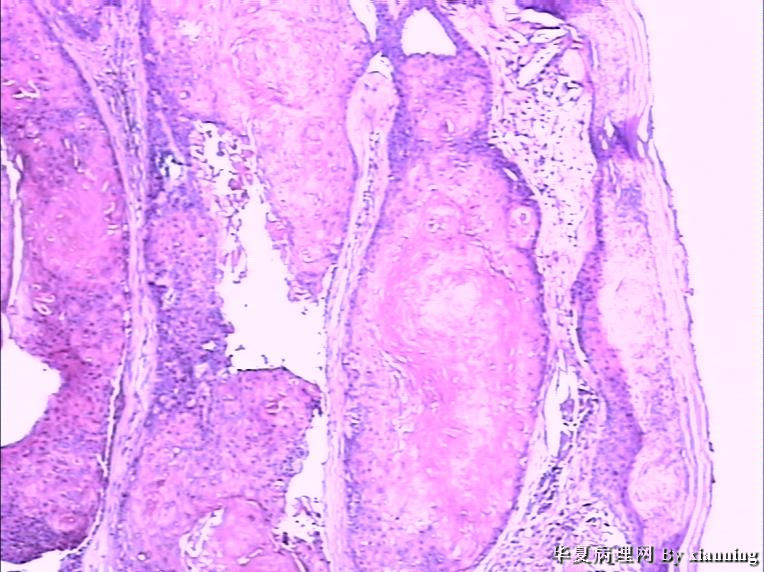

女 50岁 头皮下肿块

巨检:灰白色不规则结节0.9*0.7*0.4cm3,切面灰白色实性质地中等

名称:图3

描述:36580005